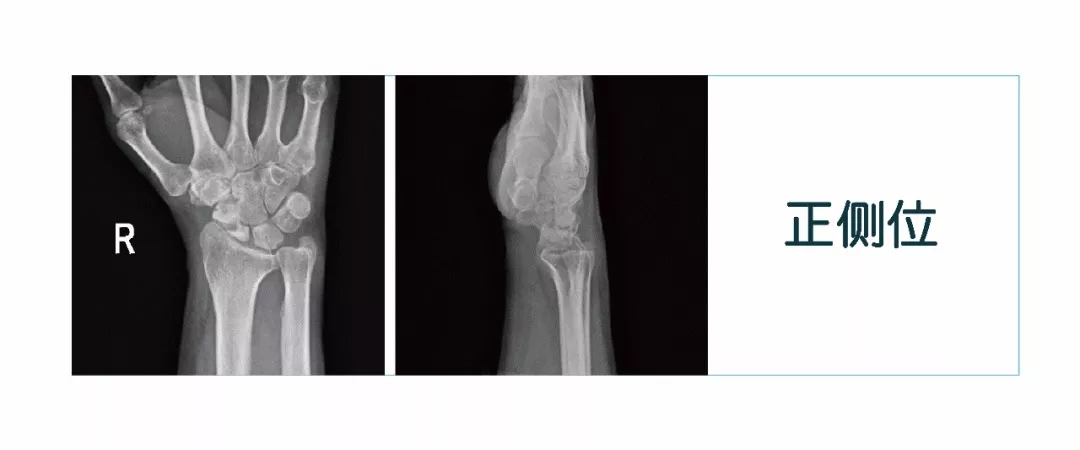

【朗润影像档案】磁共振影像病例分享(编号20180126)